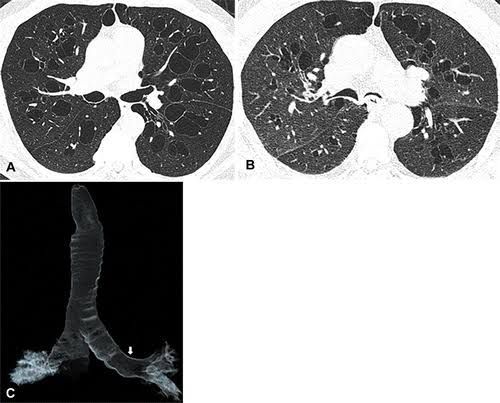

Symptoms include cough, sputum, wheeze and recurrent pulmonary infections, classically seen in the paediatric age group with selective bronchiectasis of the mid-order bronchioles. The literature describing diagnosis of Williams–Campbell syndrome in adult population is very sparse.